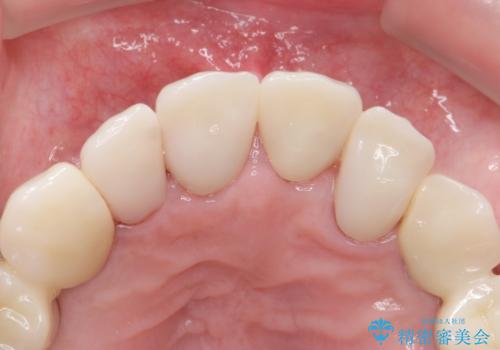

審美的な仕上がりと自然な咬み心地に喜んで頂けました。

治療前は口元を隠すようにお話しされていたのですが、治療後はそれもなくなり、満面の笑顔を見せて下さいました。

クラウンの種類:オールセラミッククラウン スタンダード